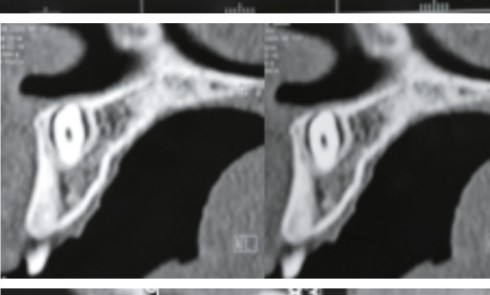

Article réservé à nos abonnés À propos d’une image radio-opaque du maxillaire

1. Quel diagnostic évoquez-vous ? a. Un ostéome b. Un améloblastome c. Un odontome complexe d. Un odontome composé e. Aucune...

Article réservé à nos abonnés Mesiodens anastrophique : quelle prise en charge ?

Les dents surnuméraires sont des anomalies de nombre qui représentent un taux d’incidence variant entre 0,15 % et 3,9 %. Elles peuvent...